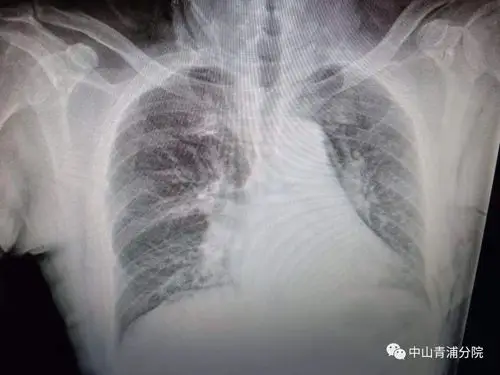

图1:胸片示一个1.3厘米的结节,箭头所示).